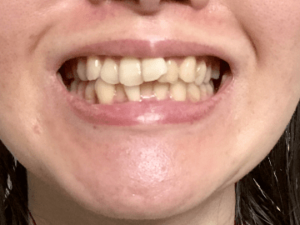

④ 歯並びの影響(特に乱ぐい歯)

歯並びがデコボコしている(叢生)場合、列から飛び出している歯が常に頬の粘膜に当たり続けるため、そこだけ部分的に白くなることがあります。また、顎が小さく歯列のアーチが狭い方も、頬とのスペースが窮屈になりやすいため注意が必要です。